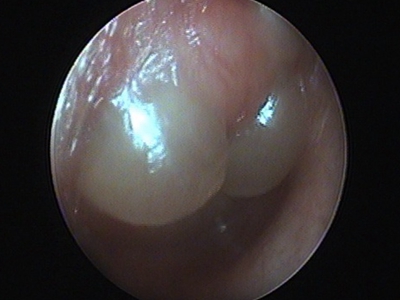

鼓膜炎又称为大疱性鼓膜炎,是鼓膜和邻近鼓膜的外耳道皮肤的急性炎症。由病毒感染所致,多发生在儿童和青年人,多为单侧,冬季多见。根据有感冒史、耳痛的症状及检查所见,容易诊断。

鼓膜炎的首发症状为外耳道剧痛,并可有轻度听力下降。随后,由于大疱破裂而有稀薄血性分泌物从外耳道流出;由于病变限于鼓膜的上皮层,未波及纤维层,故大疱破裂后无鼓膜穿孔。